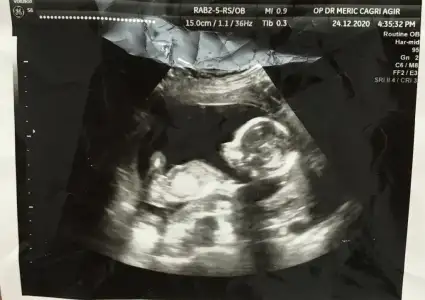

Baktım anketimde erkek demişim 11+4Merhaba 11+4 te kız demişti doktor ama dün gittiğimiz kontrolde Erkek dedi .

sende 11+4 de kız gibi demiştin :)

Sence hala kız mı erkeğe dönmüş mü ?

16+2 burda görüntü